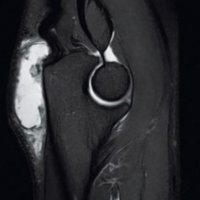

MRI is far more sensitive to detect DCO in an early stage. The most common MR-finding is bone marrow oedema in the distal clavicle, sometimes also in the articular part of the acromion, but less distinct.

Often, a hypointense line is seen in this area of clavicular bone marrow oedema, representing a subchondral fracture. AC-joint abnormalities are common, and include effusion, mild widening, intra-articular bone fragments and capsule hypertrophy. Other MR-findings are similar to those seen on radiographs, as described above.

DCO should be considered in the differential diagnosis of shoulder pain in the appropriate population. Therefore, analysis of MR arthrographic studies of the shoulder should not be restricted to evaluation of the rotator cuff and capsulolabral system, but the AC-joint should be scrutinised as well.